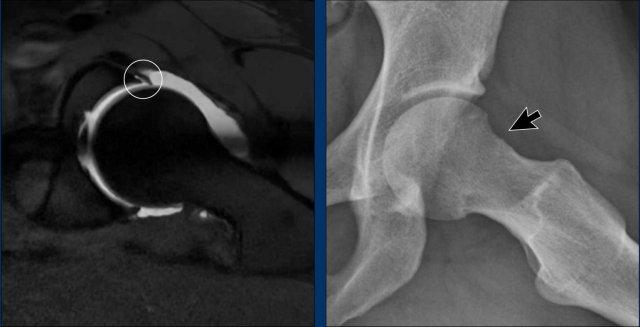

Continue with the MR-arthrogram…

Sau đó, chụp cộng hưởng từ khớp được thực hiện, cho thấy rách sụn viền ở vùng trước trên.

Ban đầu, bệnh nhân được điều trị bảo tồn bằng vật lý trị liệu, nhưng kết quả không đạt yêu cầu.

Sau đó, một thủ thuật nội soi khớp đã được thực hiện, bao gồm việc tạo hình lại chỗ nối chỏm-cổ xương đùi (mũi tên), mang lại sự cải thiện đáng kể.

Hình ảnh

Hình ảnh bên trái là MRI xương/thời gian echo bằng không (ZTE).

Đây là một kỹ thuật chụp MRI đặc biệt để khảo sát xương.

Các hình ảnh trông khá giống với hình ảnh CT và có thể được thực hiện như một phần của chụp MRI-arthrogram khớp háng.

Hình ảnh cho thấy một gai xương nhỏ (mũi tên đen).

Cuộn qua các hình ảnh của MRI-arthrogram ở phía bên phải.

Có một tổn thương sụn ở phía ổ cối (mũi tên vàng).